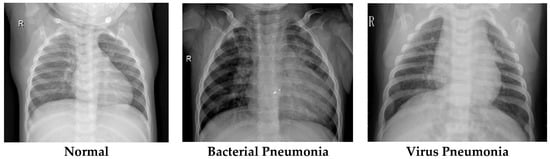

1. Introduction

2.5. Dataset